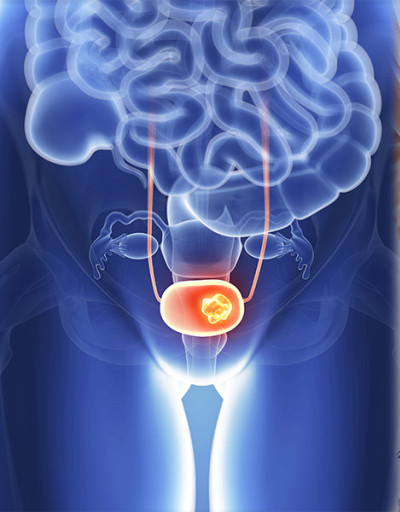

전립선에 좋은 음식 나이가 들면서 전립선 비대증이나 전립선암과 같은 질환에 노출될 위험이 커지므로, 평소 식단 관리를 통해 전립선 건강을 챙기는 것이 매우 중요합니다. 지금부터 전립선 건강을 지키는 10가지 효과적인 음식을 꼼꼼히 살펴보고, 건강을 위한 첫걸음을 함께 시작해 볼까요? 👨⚕️

- 정기적인 검진: 특히 50세 이상 남성은 정기적인 전립선 검진을 통해 미리 질환을 예방해야 합니다.